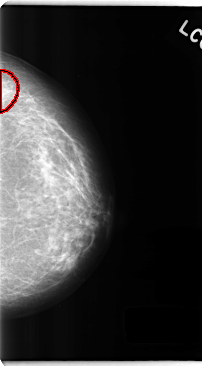

ics_version 1.0 filename C-0241-1 DATE_OF_STUDY 22 2 1995 PATIENT_AGE 63 FILM FILM_TYPE REGULAR DENSITY 2 DATE_DIGITIZED 28 4 1998 DIGITIZER LUMISYS LASER SEQUENCE LEFT_CC LINES 4752 PIXELS_PER_LINE 2624 BITS_PER_PIXEL 12 RESOLUTION 50 OVERLAY LEFT_MLO LINES 4744 PIXELS_PER_LINE 2512 BITS_PER_PIXEL 12 RESOLUTION 50 OVERLAY RIGHT_CC LINES 4712 PIXELS_PER_LINE 2656 BITS_PER_PIXEL 12 RESOLUTION 50 NON_OVERLAY RIGHT_MLO LINES 4728 PIXELS_PER_LINE 2656 BITS_PER_PIXEL 12 RESOLUTION 50 NON_OVERLAY |

FILE: C_0241_1.LEFT_CC.OVERLAY TOTAL_ABNORMALITIES 1 ABNORMALITY 1 LESION_TYPE MASS SHAPE IRREGULAR MARGINS ILL_DEFINED ASSESSMENT 4 SUBTLETY 3 PATHOLOGY BENIGN TOTAL_OUTLINES 1 BOUNDARY |